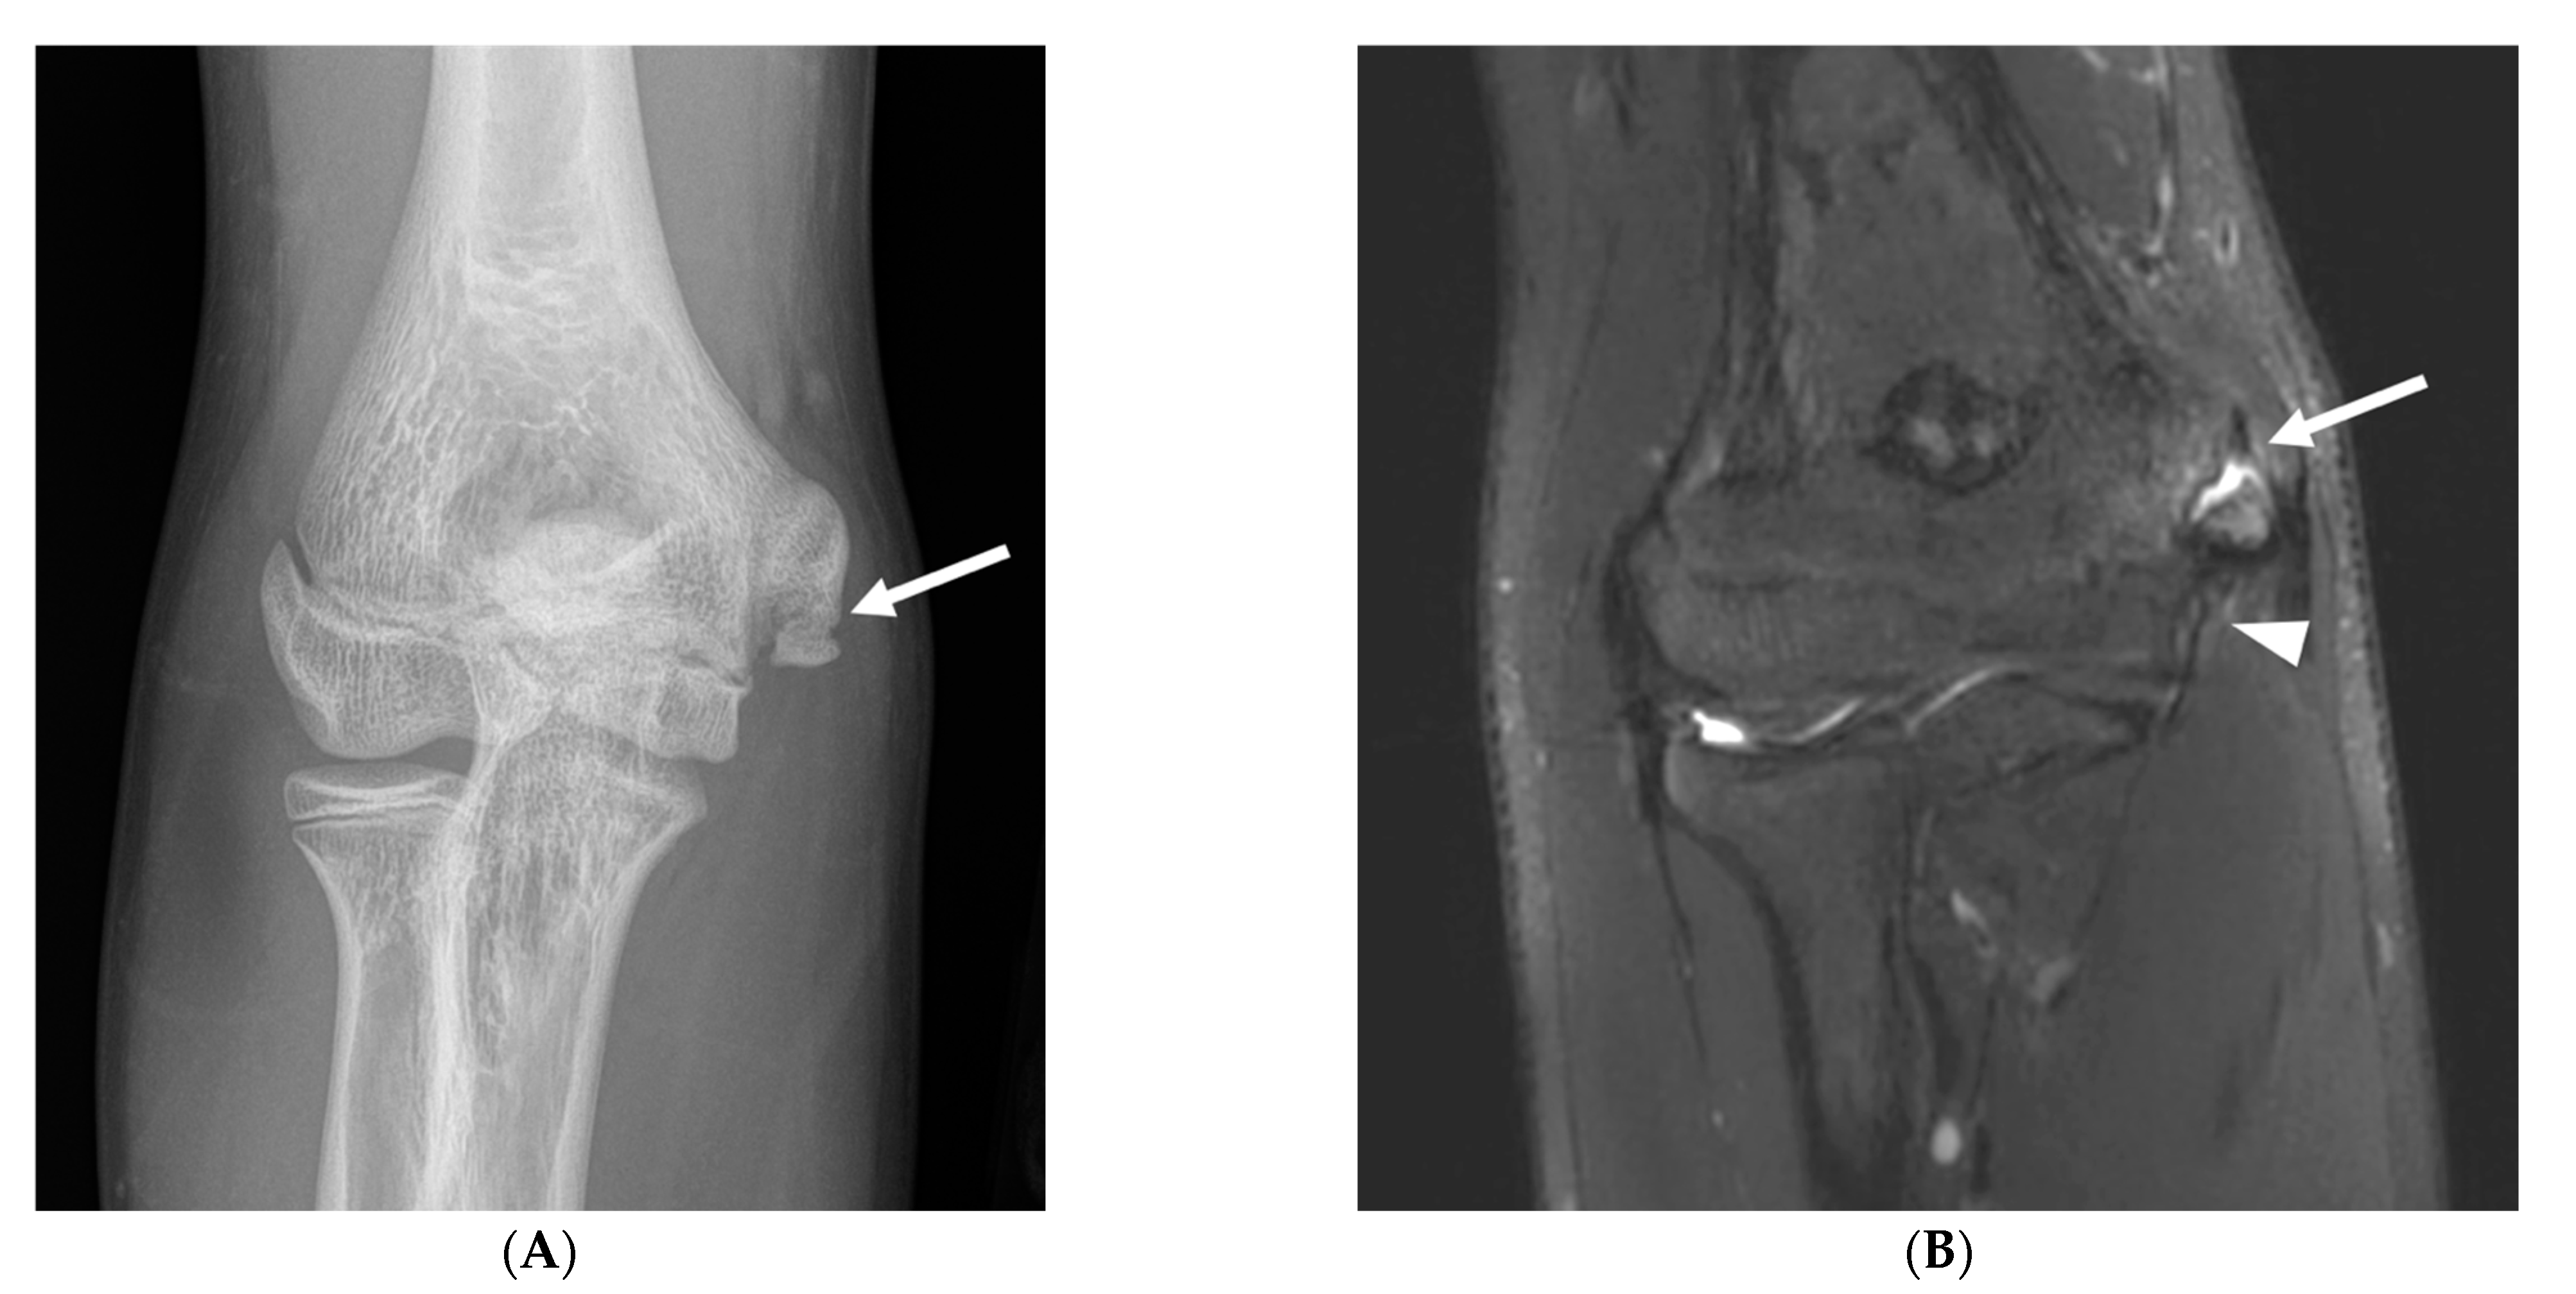

Osseous abnormalities resulting from valgus extension overload were seen more frequently in younger athletes. Medial epicondylar apophysitis and acute apophyseal avulsion injuries from medial tension overload were only observed in athletes in subgroup 1 (Figure 3), although evidence of chronic avulsion injury was seen in the older age groups. Osseous findings from radiocapitellar overload were also seen most frequently in athletes in subgroup 1 (Figure 4), whereas posterior humeroulnar chondral injuries occurred with greatest frequency in subgroup 2.

Figure 3.

A 12-year-old right-hand-dominant male baseball pitcher who developed acute medial elbow pain during a pitching lesson. (A) AP radiograph demonstrates an acute avulsion fracture of the medial epicondylar apophysis (arrow). (B) Coronal fat-saturated T2-weighted image demonstrates an acute avulsion fracture of the medial epicondylar apophysis (arrow). The anterior band of the ulnar collateral ligament remains intact (arrowhead).